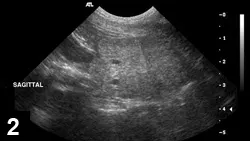

FIGURE 4

Sagittal view of a prostate in a castrated dog. Prostatic mineralization suggests neoplasia.

• Diagnosis of PN can be supported by intraprostatic mineralization and complex parenchymal changes on ultrasonography (Figure 4).